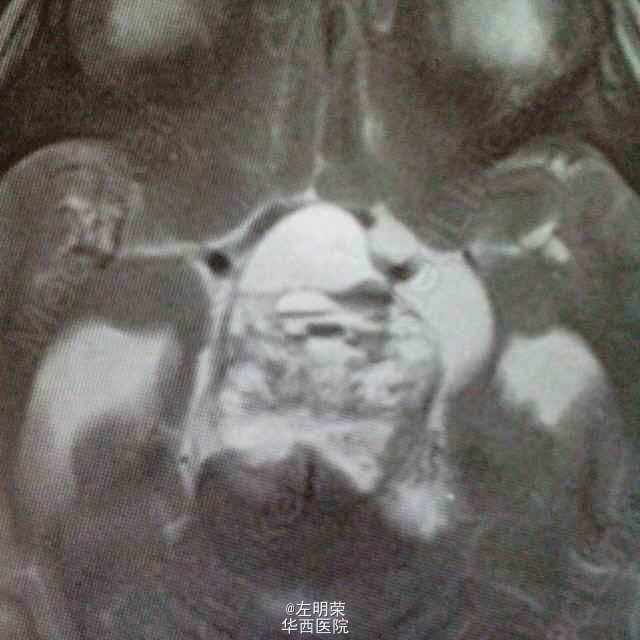

女,6岁,以间断头痛3个月余,加重2个月之主诉入院。MRI示:桥前池-鞍上池-三脑室内巨大不规则均匀强化影,鞍背骨质可见破坏,病灶内可见囊变坏死区。可见脑干及病灶周围实质明显受压移位,病灶与脑实质分界清楚;考虑诊断脊索瘤,颅咽管瘤,神经鞘瘤。术中见肿瘤囊实性,血供丰富,边界尚清,位于鞍背上方,脑干前方,与基底动脉,大脑后动脉粘连紧密,给予全部切除;病理示:神经鞘瘤。